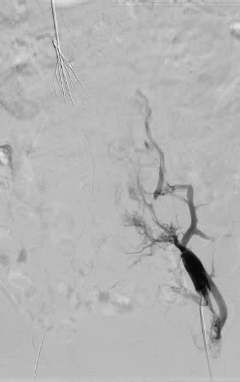

多学科会诊后,结合患者实际情况,田轩院长带领团队制定了双侧髂静脉血管球囊扩张成形 + 经皮机械血栓清除术 + 下腔静脉球囊扩张成形术的诊疗方案。

手术在 DSA 引导下开展,团队按照既定方案规范操作,小心清除滤器周围血栓,重建静脉通道,全程注重操作精准性与安全性,手术顺利完成。